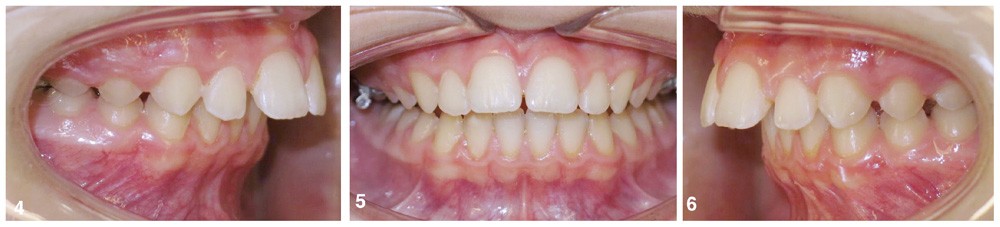

Le parodonte est fin et festonné mais l’hygiène est maîtrisée. On retrouve une endoalvéolie maxillaire relative à la classe II, une supraclusion incisive d’origine mandibulaire, une biproalvéolie incisive, un surplomb incisif de 9 mm associé à une classe II dentaire sévère (fig. 3 à 6).

La prise en charge a pour objectif d’obtenir une classe I dentaire en favorisant la croissance sagittale de la mandibule. Étant donné l’échec de la phase interceptive mettant en doute la coopération de la patiente, nous décidons de ne pas réaliser une nouvelle phase orthopédique à l’aide d’un appareil amovible mais de mettre en place un dispositif multi-attaches.

La patiente, non réglée, présente un stade C3 selon la classification de Lamparski concernant le stade de maturation des vertèbres cervicales [2], en effet on retrouve une concavité inférieure de la vertèbre C3 mais pas encore au niveau de C4. On se situe donc légèrement en avant du pic pubertaire qui survient dans 93 % des cas entre les stades C3 et C4 selon Bacetti [3]. Ainsi, il sera possible chez cette patiente, après la préparation des arcades, d’obtenir une réponse orthopédique optimale lors de la mécanique de classe II à l’aide des propulseurs mandibulaires.